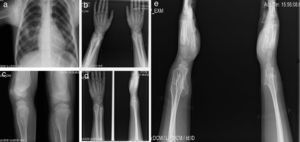

Paciente de sexo femenino, de 40 años de edad; desde que nació los padres percibieron muchos chasquidos articulares al cargarla, sin dolor aparente. A los 3 años de edad se detectó protuberancia incapacitante en rodilla izquierda que le producía dolor al caminar, por lo que requirió cirugía. A los 16 años desarrolló una deformidad en los tobillos (región maleolar externa de 4×4×3cm y región de tibia) que le producía dolor, por lo que ameritó cirugía correctiva. A los 20 años presentó engrosamiento y deformidad de las muñecas, que llegó a medir 4×5×2cm. Al final de su crecimiento óseo se determinó que la longitud del brazo derecho era 2cm mayor que la del izquierdo (fig. 2).

Caso 1 (II2). Paciente femenino de 40 años (madre) que presenta excrecencias óseas (exostosis) con manifestaciones en la unión esterno-costal de las primeras costillas y la parte superior del arco costal posterior (a), protuberancias óseas en cuellos femorales y región intertrocantérica con deformidad ósea (b), exostosis en región proximal de húmero (c) y tercio distal de fémur bilateral en región postero-medial y en borde postero-externo de tibia izquierda (d).